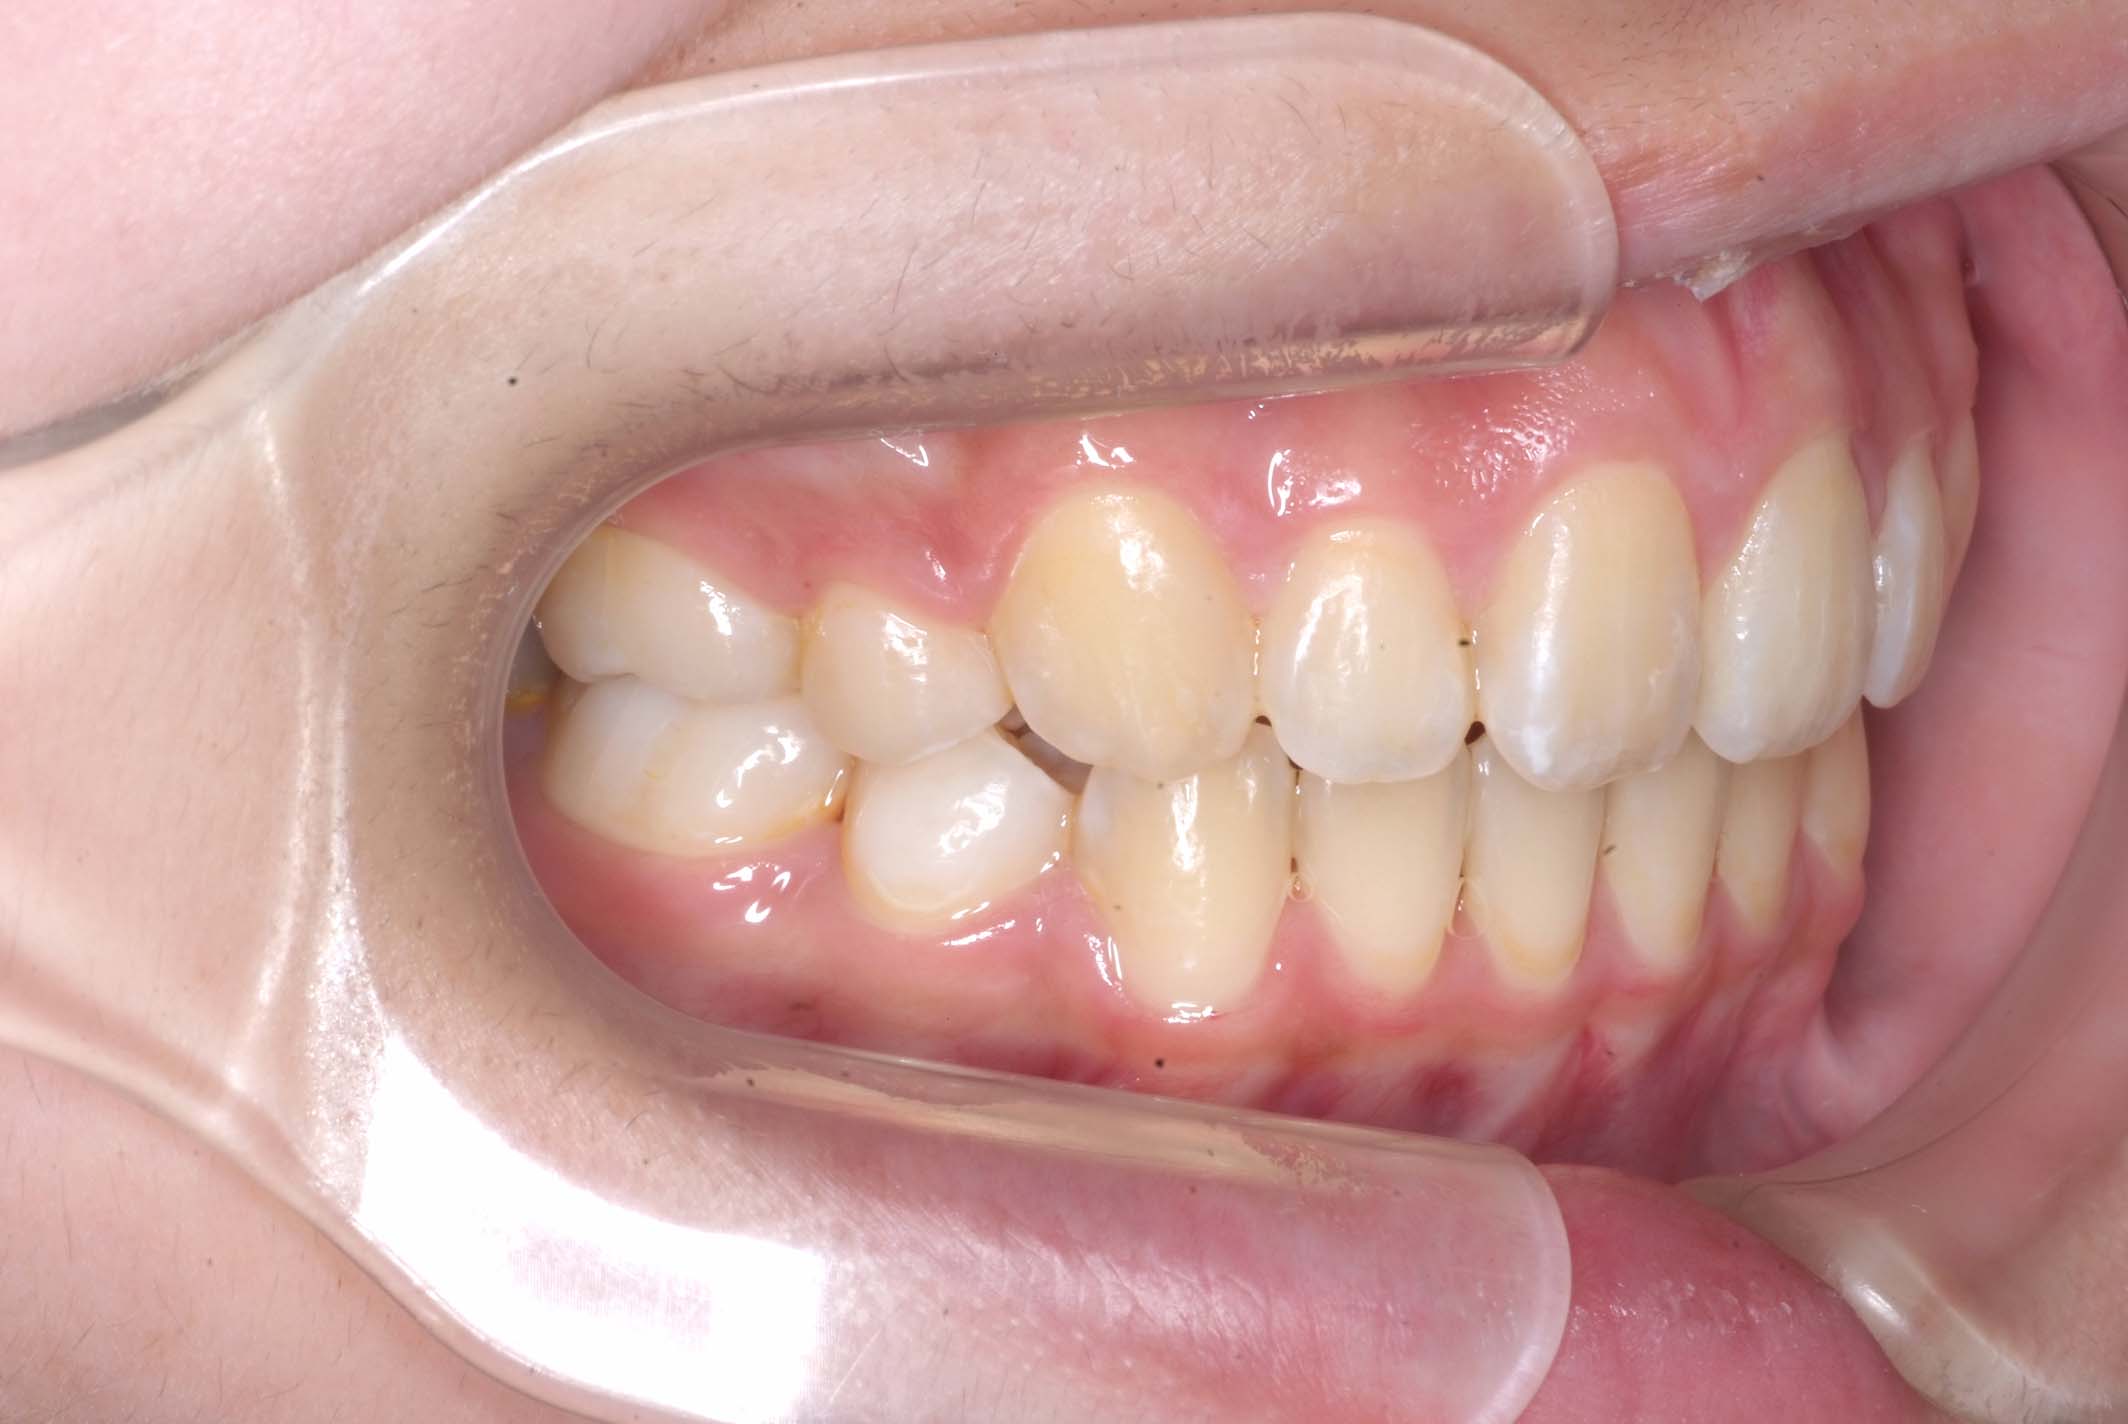

初診時年齢8才の女子で、前歯部開咬を気にして来院されました。

検査の結果、前歯部開咬と正中離開と上下顎前歯唇側傾斜を伴うアングルⅡ級1類不正咬合と診断しました。

前期治療は、リンガルアーチで正中離開を改善し、その後は歯列矯正用咬合誘導装置(マイオブレース)を使用して舌のトレーニングを行いました。後期治療は、上下左右4番を抜歯の上、セルフライゲーションブラケット装置(クリアティ・ウルトラ)で行いました。治療期間は前後期合わせて6年6ヶ月でした。通院回数:60回。